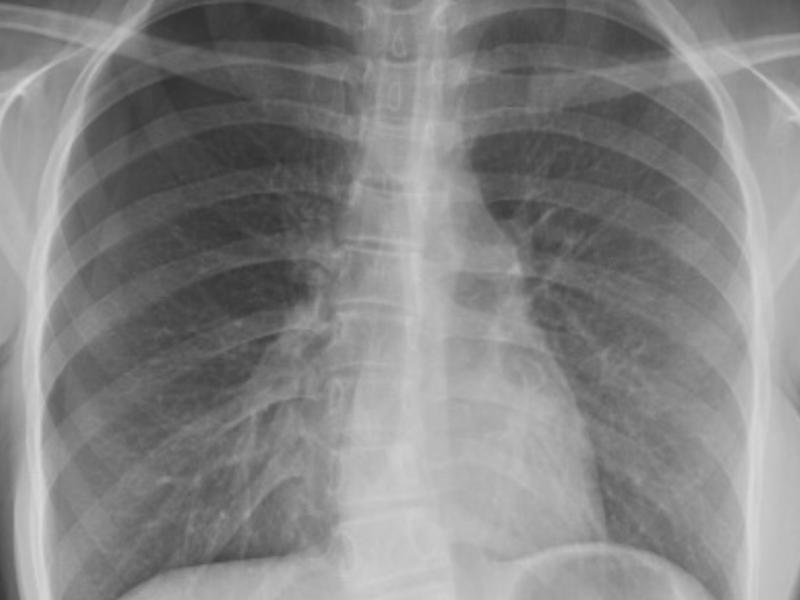

A 16 yo female presents with shortness of breath that